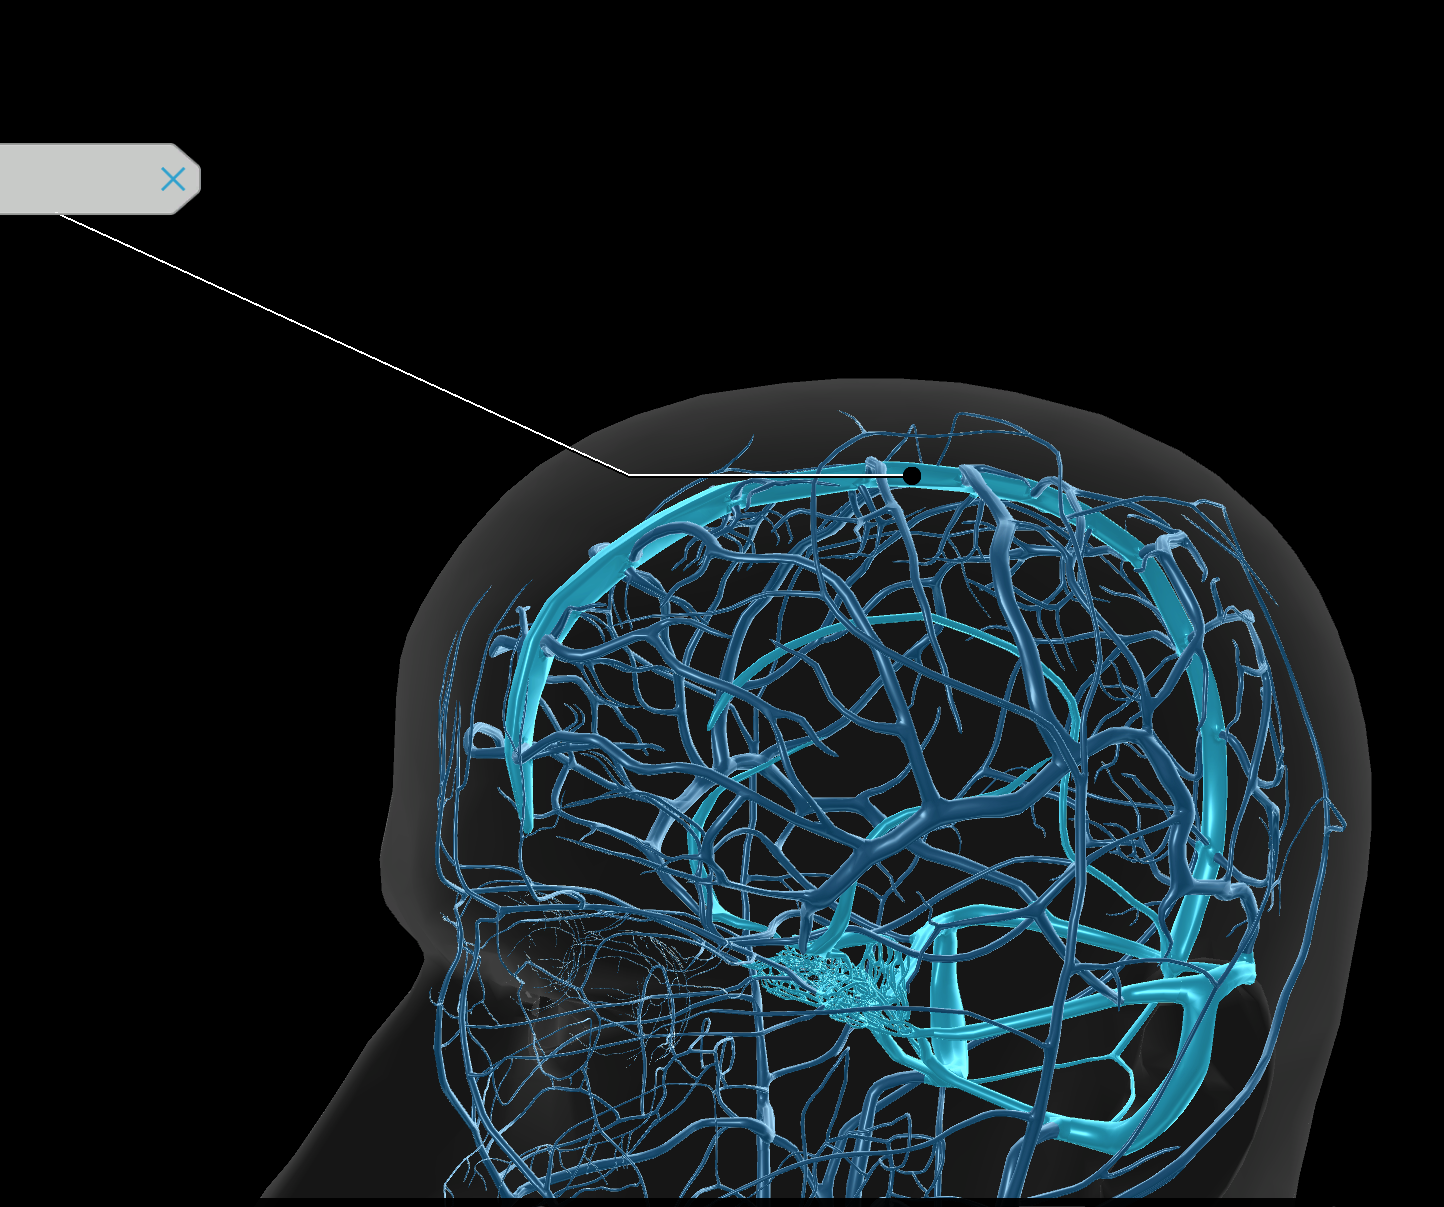

Internal Jugular Vein

External Jugular Vein

Circle of Willis

Venous Sinuses